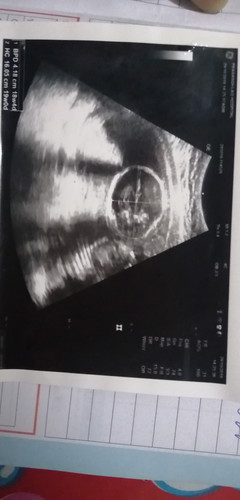

เธอจะเป็นผู้หญิงหรือชายกันนะ

นี่ภาพกระโหลกจ้า ดูเพศไม่ได้

ยินดีด้วยจ้า